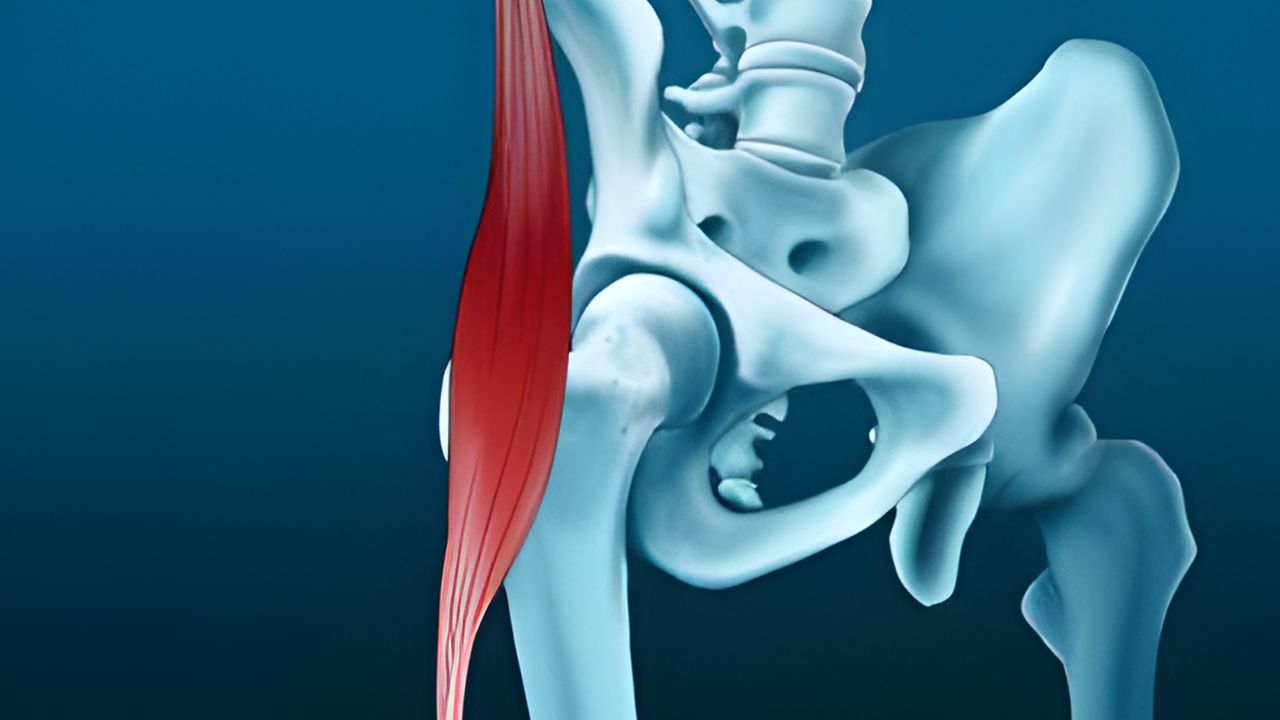

Principais causas do ressalto no quadril O encurtamento muscular e o desequilíbrio biomecânico são as causas mais comuns. A tensão excessiva na banda iliotibial ou no tendão do iliopsoas faz com que essas estruturas “saltem” sobre os ossos durante o movimento. Além disso, alterações intra-articulares, como lesões no labrum ou corpos livres, também podem gerar travamentos e estalos profundos, limitando a função articular.